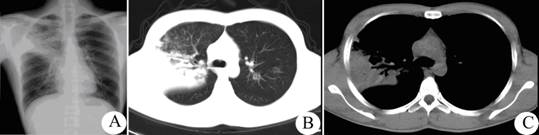

男性患者,32岁,发热、咳嗽3天,体温最高39、8℃,胸片及ct检查见下图。该病例应诊断为哪种疾病,诊断依据是什么?

段性均匀渗出影,支气管气像,临床资料佐证——大叶性肺炎。